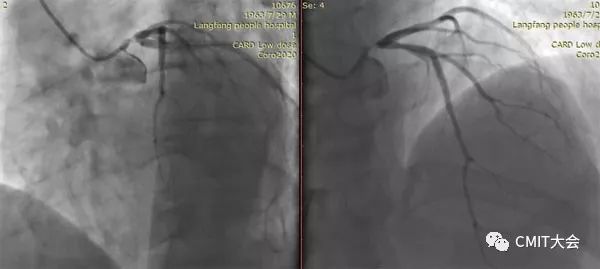

➢ CASE 6

经股动脉途径TIG,非选择造影如果能清晰显影,可不做超选造影

➢ CASE 7

经左侧桡动脉途径JR4.0,非选择造影如果能清晰显影,可不做超选造影